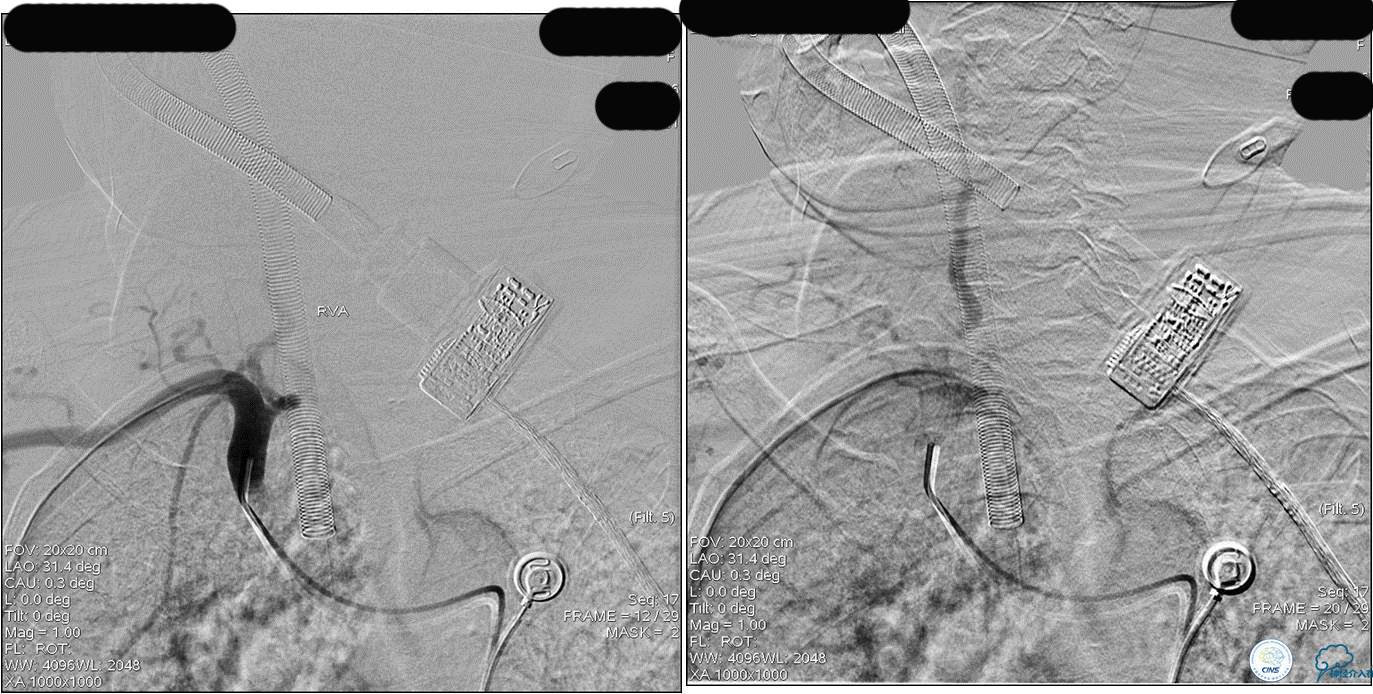

》DSA资料(第3次取栓)

第3次取出血栓

》DSA资料(第3次取栓后,发病10h)

》DSA资料(视察30min后,左椎造影)